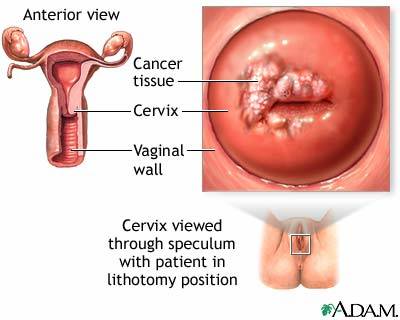

รูปที่ 1 โรคมรณะอย่างมะเร็งปากมดลูกอาจนำมาด้วยอาการเพียง “ตกขาว” หรือมีเลือดออกกะปริดกะปรอยเท่านั้น

รูปที่ 2 ก้อนเนื้อมะเร็งปากมดลูกของจริงที่ถูกตัดออกมาพร้อมปากมดลูก แน่ใจหรือว่าเป็นตกขาวปกติ? “คงเป็นตกขาวปกติ ไม่มีอะไรหรอก” ที่กล่าวว่าเป็นการอ้างก็เพราะเป็นธรรมดาของหญิงไทยที่มักจะขี้อาย เรียบร้อยเหมือนผ้าพับไว้บ้าง ไม่เหมือนบ้าง แต่ก็มักจะอายกันเป็นส่วนใหญ่ ผิดกับเด็กหญิงอเมริกันที่เริ่มตรวจภายในกันตั้งแต่วัยทีนเอจ แต่ก็เป็นข้อดีไม่น้อยเพราะทำให้อัตราการตายจากโรคมะเร็งปากมดลูกไม่สูงเท่า ในคนไทยเรา เพราะเมื่อตรวจภายในได้ส่องเข้าไปดูถึงปากมดลูก ถ้าเห็นติ่งเห็นก้อนอะไรผิดปกติก็สามารถตัดและแก้ได้ทันตั้งแต่เนิ่นๆ มะเร็งยังไม่ทันลามไปต่อมน้ำเหลืองก็สกัดได้ทันก่อน พอมาเห็นคุณย่าคุณยายบ้านเราที่กว่าจะตรวจพบมะเร็งก็ “สายเสียแล้ว” ถึงรู้สึกเสียใจและเสียดายมากๆทีเดียวครับ